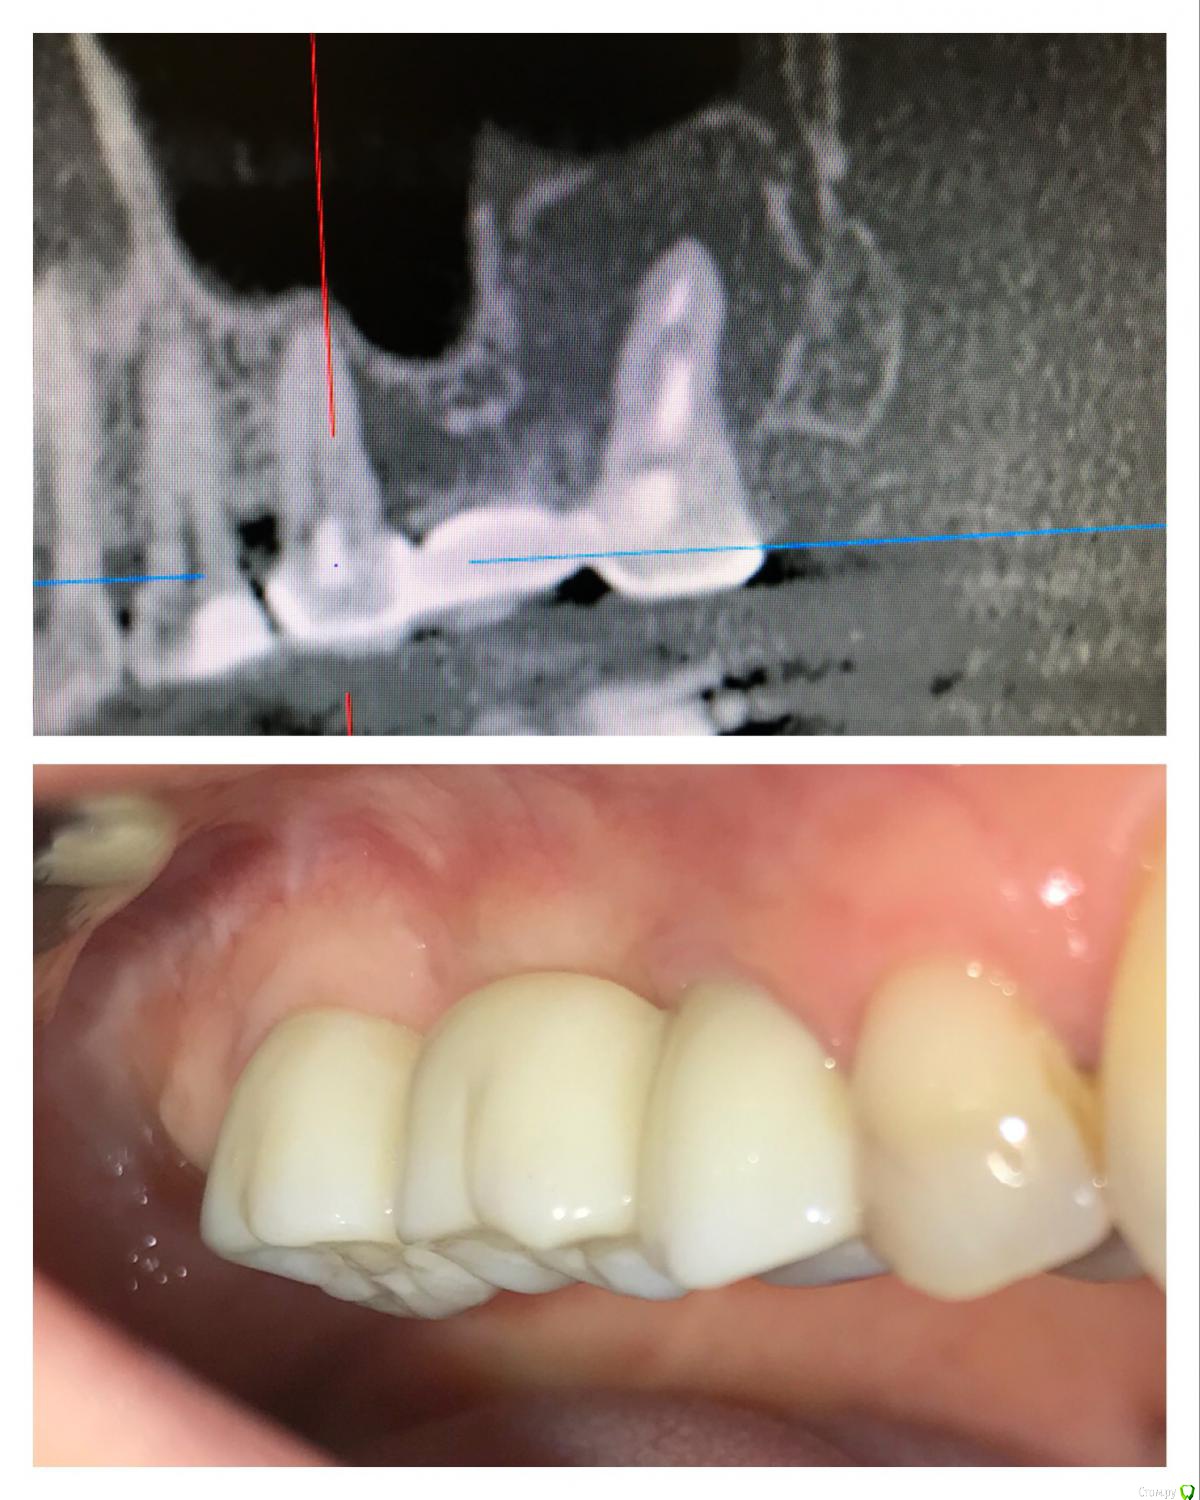

vse32 Опубликовано 6 ноября, 2019 Поделиться Опубликовано 6 ноября, 2019 Я стоматолог терапевт, поэтому вопрос почти как от обывателя.16 зуб, женщина около 35 лет (не видела ее, коллега мужа по работе). В сторонней клинике сделали ОПТГ и КТ и рекомендовали удаление с одномоментной имплантацией. Со слов женщины предложен корейский имплантат за х рублей + подсадка за х рублей. Или американский имплантат за 2х рублей без подсадок.Вопрос - нормально ли это делать одномоментно при наличии кистогранулемы (вне обострения).Лечить эндодонтически могу, но сомневаюсь в гарантийности работы. Ссылка на комментарий

vse32 Опубликовано 7 ноября, 2019 Автор Поделиться Опубликовано 7 ноября, 2019 И что посоветовать выбрать пациентке? Корейский имплантат за х рублей + подсадка за х рублей. Или американский имплантат за 2х рублей без подсадок. Американский, предположу, что Bicon. Его вроде за 80.000 предлагали. Ссылка на комментарий

Irouil Опубликовано 7 ноября, 2019 Поделиться Опубликовано 7 ноября, 2019 Нужно полноценно кт смотреть. С байконом не работал, но слышал плохие отзывы на ортопедию. Корейские винты сейчас, в основном, довольно добротные. Выяснить бы в чем причина разницы в хирургических протоколах Ссылка на комментарий

колесников Опубликовано 8 ноября, 2019 Поделиться Опубликовано 8 ноября, 2019 И что посоветовать выбрать пациентке? Корейский имплантат за х рублей + подсадка за х рублей. Или американский имплантат за 2х рублей без подсадок. Американский, предположу, что Bicon. Его вроде за 80.000 предлагали. предположу что американский- это Нобель актив . Хотя...если взять толстый байкон,то он займёт собой весь объём лунки и графт не нужен. Но мне кажется Байкон надо сверху графтом засыпать. Я бы рекомендовал корейский с графтом Ссылка на комментарий